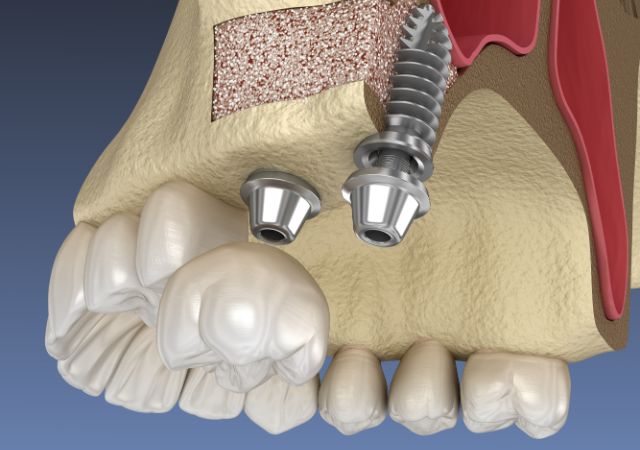

インプラントは、あごの骨にチタン製の人工の歯の根を入れ、その上に歯を作る治療で、自然な見た目としっかり噛める感覚が特徴です。ブリッジのように健康な隣の歯を削る必要がないことも大きなメリットです。

インプラントは顎の骨の中にインプラント体(ネジ)を植立することで機能しますが、インプラントを行う予定の部位の顎の骨が不足している場合は、人工の骨を補填し骨の幅を十分に確保した状態でインプラントを埋入する必要があります。

インプラントは、失った歯の部分に人工の歯根(チタン製)を埋め込み、その上に人工の歯を装着する治療法です。見た目も機能も天然の歯に近く、しっかり噛むことができます。